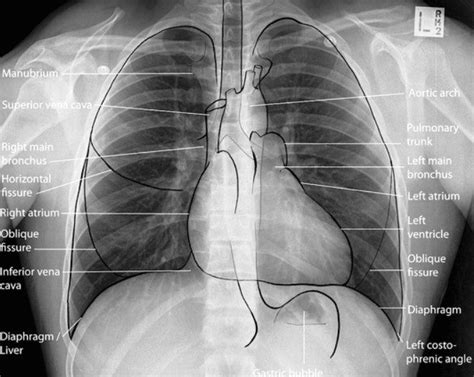

When an X-ray beam is directed at your body, different tissues absorb the radiation to varying degrees. Dense materials, like bone, which are packed tightly together, absorb more X-rays. Softer tissues, like muscles and organs, absorb fewer X-rays. The X-rays that aren’t absorbed pass through to a detector on the other side, usually a digital sensor or photographic film. This creates a radiograph , which is essentially a shadow picture. Bones appear white or light gray because they block the X-rays, while air-filled areas, like your lungs, appear black because the X-rays pass through them easily. Everything else falls somewhere in between, giving us a detailed, albeit grayscale, image of your internal structures. It’s this difference in absorption that allows doctors to see things like fractures, infections, or even foreign objects inside you without having to cut you open. Pretty neat, huh?

So, we know what X-rays are and how they’re made, but did you know there are different ways they’re used? Yep, imaging isn’t a one-size-fits-all deal with X-rays. The most common type you’ll probably encounter is the standard plain film X-ray , which is what we’ve been talking about – that black-and-white snapshot of your bones and some organs. These are great for quick checks, like seeing if you’ve broken a bone or looking for signs of pneumonia in your lungs.